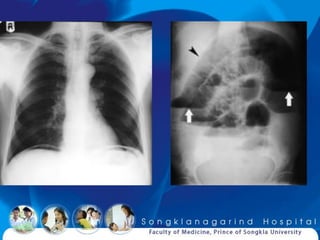

Film acute abdomen

10-38% confirm diagnosis

Gallstone Ileus

Portal vein gas

Case 2

Female 53 years old

Underlying HT

LLQ abdominal pain for 1 day

V/S BP 140/80 P 90 RR 24

Abd: LLQ pain, guarding ?

CVA: tenderness Lt.

UA: microscopic hematuria

Diclofenac  improved

Recurrent 2 times in 3 days

What is diagnosis ?

Hematuria may be seen in

abdominal aortic aneurysm (30%)